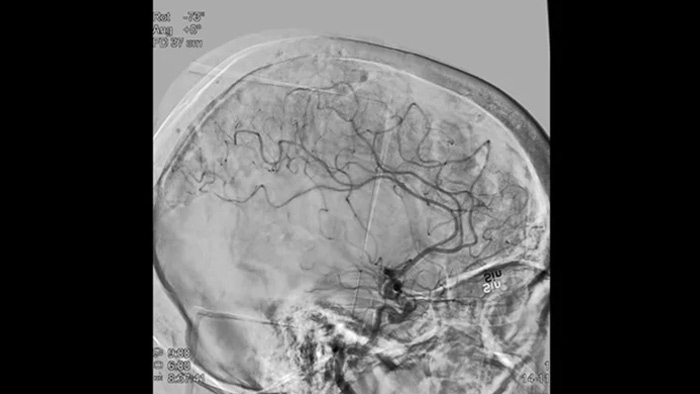

Четкие изображения при помощи 2D DSA с использованием технологии ClarityIQ

2D DSA с использованием технологии ClarityIQ

Технология ClarityIQ применяет опцию автоматической компенсации артефактов движения во время проведения DSA в режиме реального времени, чтобы создавать четкие изображения сосудов. Это способствует принятию верных решений во время операций по лечению инсульта.

Визуализация DSA

Высококачественная визуализация в режиме DSA позволяет оценить, был ли тромб полностью удален и произошло ли растворение сгустков крови в головном мозге. Врачам предоставляется возможность проверить восстановление кровотока в области ишемической полутени, а также наличие кровотечений в периоперационный период.